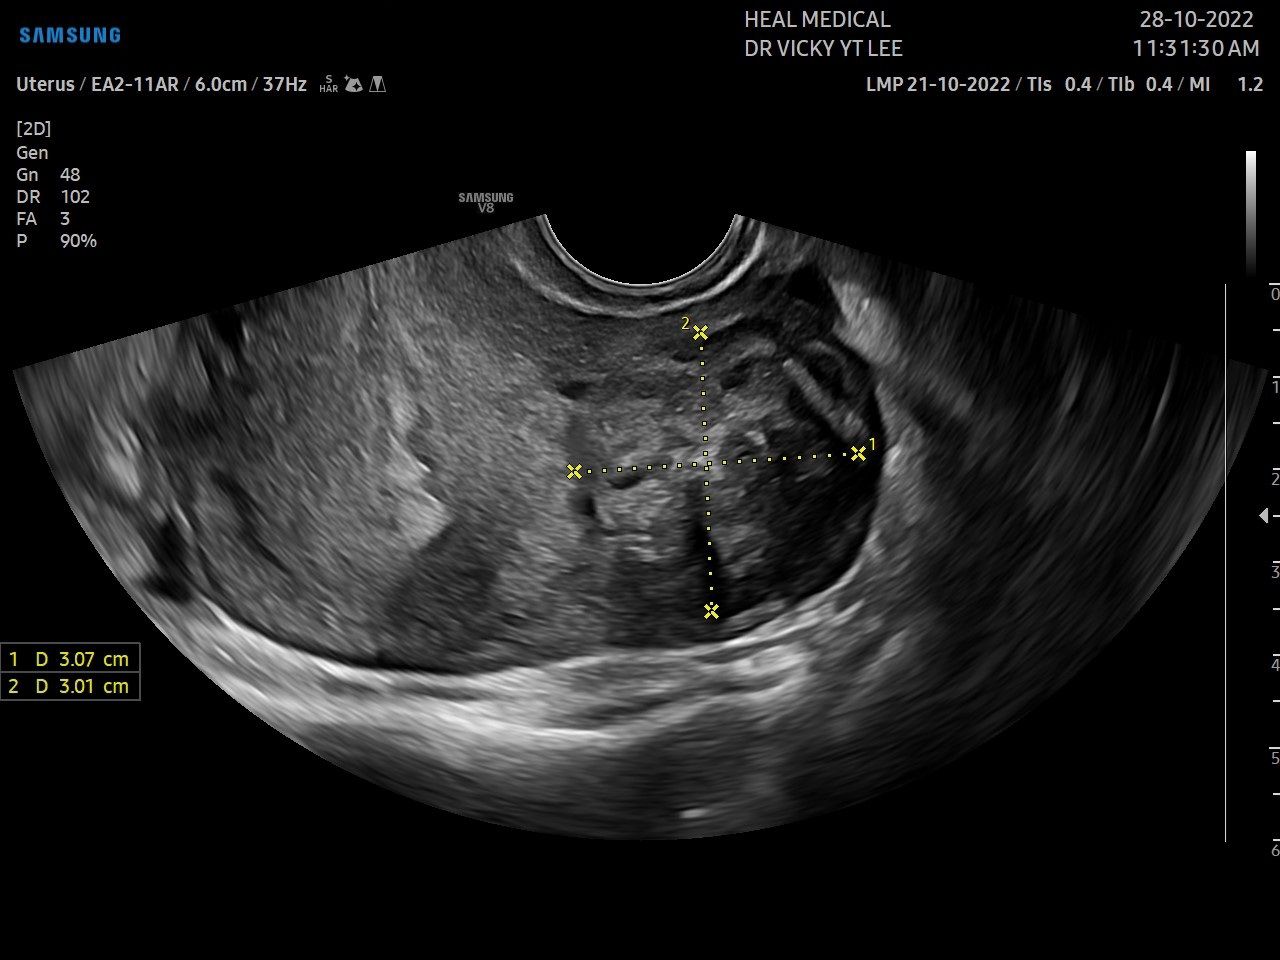

2.JPG

想了解是否患有子宮肌瘤,要透過婦產(chǎn)科腹部或經(jīng)陰道的超聲波檢查,確認肌瘤的大小和位置。